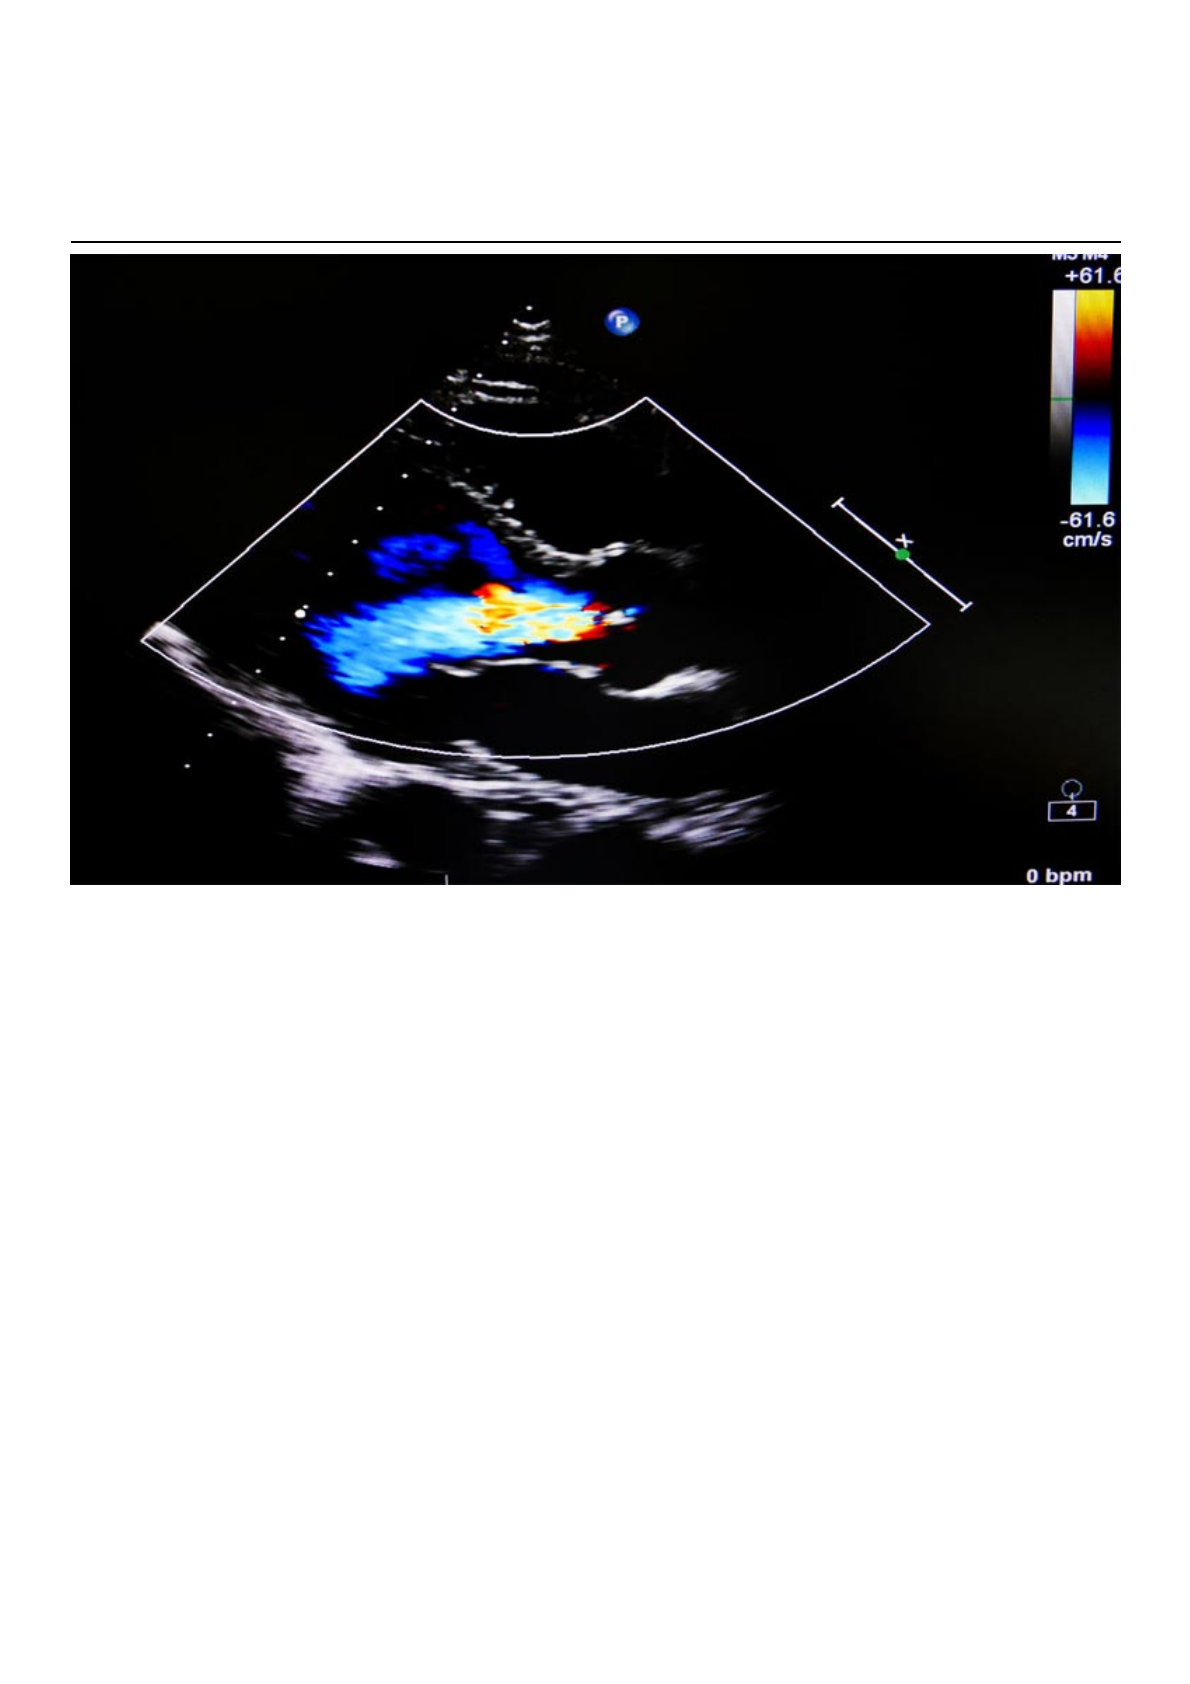

Quando há algum problema no fechamento de uma das válvulas, permitindo retorno de sangue

para uma das câmaras, chamamos de regurgitação ou insuficiência. No caso de um problema no

fechamento da válvula mitral, damos o nome de regurgitação mitral.

O prolapso da válvula mitral é uma das causas de regurgitação mitral, pois os folhetos se empurram e

não vedam completamente a passagem de sangue.

O diagnóstico do prolapso mitral é confirmado facilmente pelo ecocardiograma.